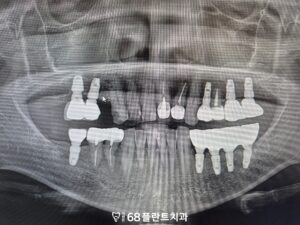

◆ 전 > 후 ◆

치료가 모두 완료된 후, 환자분께서는

왼쪽 위 자연치아가 있을 당시부터

아래 브릿지 치아에 불편감이 있었지만,

치아가 상실된 이후 통증이 다소 줄어들면서

치료를 미루어 오셨다고 말씀하셨습니다.

그러나 이번에 위쪽 치료와 함께

임플란트로 교체를 진행하면서

안정적으로 기능을 회복할 수 있게 되었고,

이제는 식사 시에도 편안하게 사용할 수 있어

큰 만족감을 표현해주셨습니다.